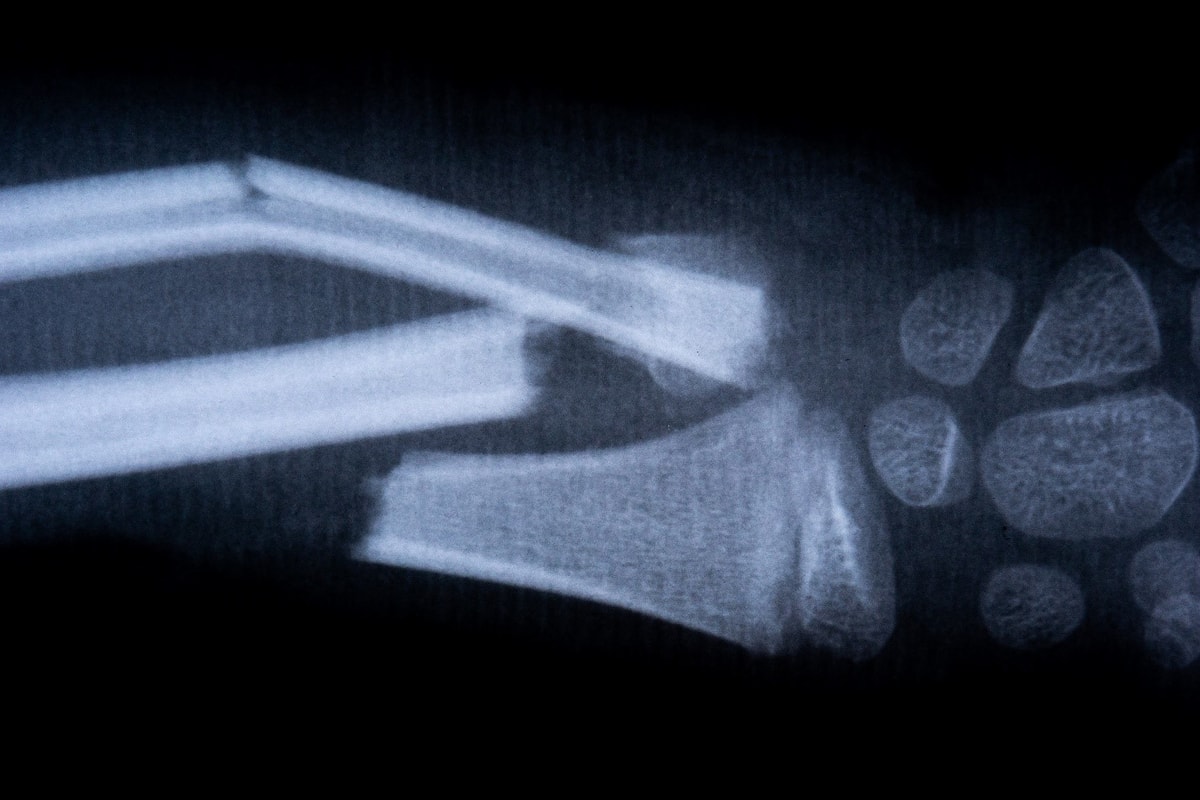

The forearm has two bones: the thumb (radius) and the elbow (ulna). They can be individually or both broken. Usually a fracture is the result of a fall on the arm, only exceptionally due to the direct action of the force.

Procedure: First, carefully stretch the broken bones by grabbing the palm and upper arm of the broken arm, then immobilize. Immobilization can be performed by inflatable splinters, classic Kramer splints or improvised immobilisers.

Pain should be suppressed by the use of analgesics.